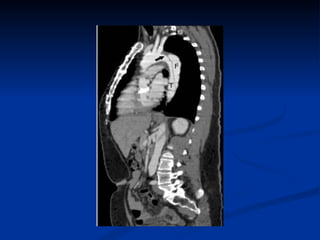

CT SCAN WITH CONTRAST Sensitivity 98-100%  Specificity 98-100% Limitations : Use of contrast Inability to identify site of tear No evaluation of aortic regurgitation Limited information on branch vessels Useful for follow-up of dissections

CT SCAN WITHCONTRAST Sensitivity 98-100% Specificity 98-100% Limitations : Use of contrast Inability to identify site of tear No evaluation of aortic regurgitation Limited information on branch vessels Useful for follow-up of dissections